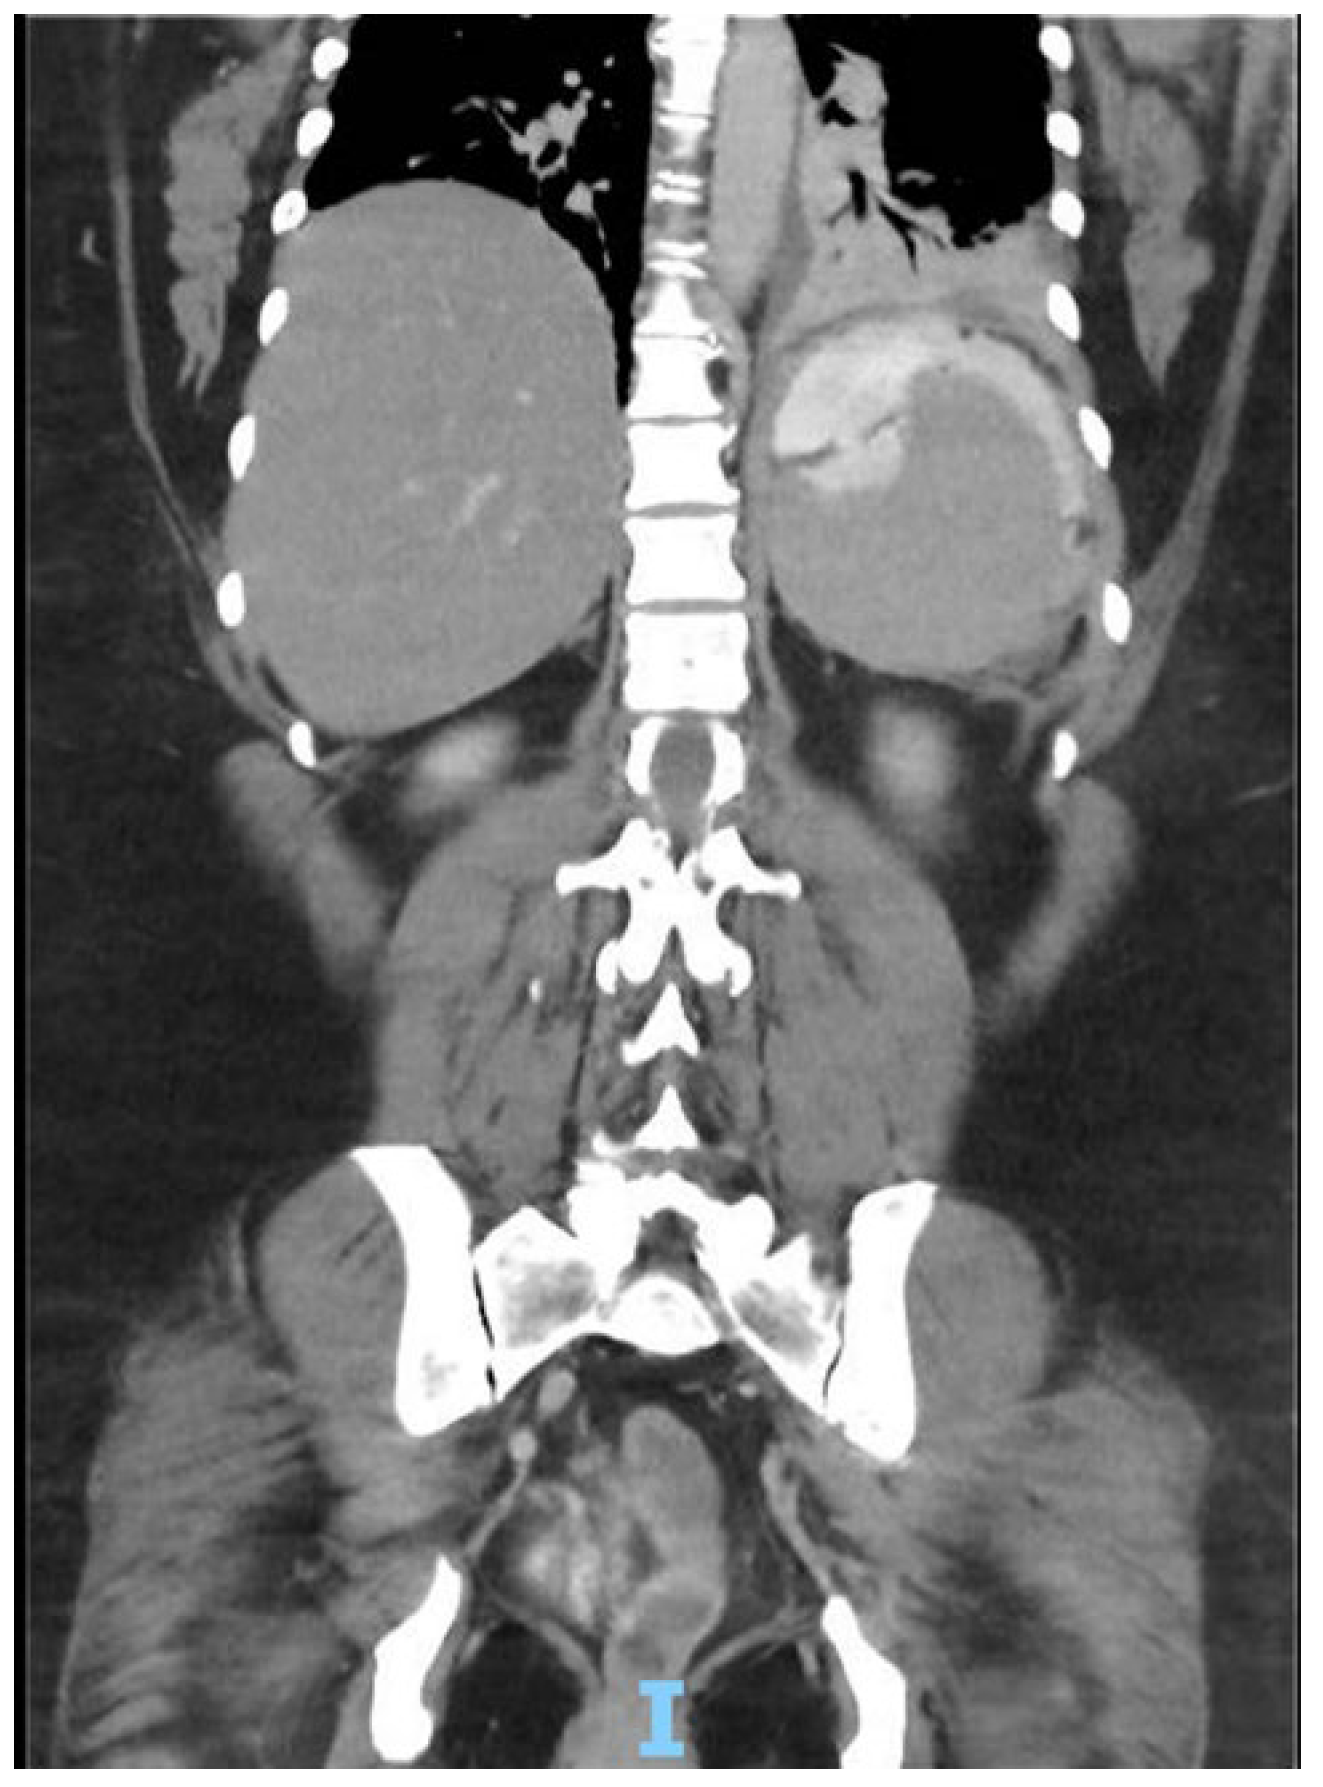

Patient arrives to the emergency room 48 hours after gastric sleeve surgery, she was admitted for abdominal pain referred to the left shoulder, a computer tomography (CT) was performed with evidence of leak at the gastroesophageal junction, a left subphrenic collection and pleural effusion of left predominance [Figure 1], she is taken to operation theatre and laparoscopic lavage and drainage is performed [Figure 2]. Treatment continues with IV antibiotics and parenteral nutrition. Thirteen days after re-intervention she presents deep venous thrombosis of the right lower limb and pulmonary thromboembolism of a segmental branch of the left lower lobe, she was managed with full anticoagulation and high flow cannula. She was then admitted to the intensive care unit (ICU) for 72 hours for observation. After stabilization is carried out, endoscopic management of the leak site with an Over-the-scope clip (OVESCO) is performed and mixed nutrition is installed, outpatient management is given with enteral nutrition for 4 weeks however the leak persists so after placement of vena cava filter, she is submitted for revisional Roux en Y gastric bypass [Figure 3]. Patient is discharged at 72 hours with complete resolution of the fistula, current follow-up at 4 months has been uneventful.

Figure 3. Intraoperative image of Roux en Y Gastric Bypass showing both gastrojejunostomy and jejunojejunostomy with no signs of immediate complications.